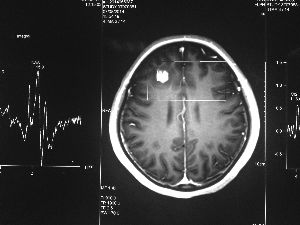

今年6月份,張敏在宿舍休息時(shí),又發(fā)起了癲癇,也是口吐白沫,渾身抽搐。送到蘇州一家大醫(yī)院,頭顱核磁共振檢查出,張敏大腦右額葉處有一處病灶,也就是大腦額頭處有個(gè)東西。

專家認(rèn)為有可能是腦瘤,但也有可能是其他的東西,具體是什么,卻沒有辦法進(jìn)一步判斷。醫(yī)院開了一點(diǎn)控制癲癇的藥物,讓張敏服用,并叮囑隨時(shí)復(fù)查。

腦袋里的東西,到底是腫瘤還是其他什么東西,這個(gè)謎像個(gè)石頭一樣,壓得張敏一家人喘不過氣。7月份,張敏一家又來到南京腦科醫(yī)院求醫(yī),第三次檢查后,醫(yī)生覺得很像是寄生蟲。不過,影像的檢查,只能作為醫(yī)生推測(cè)的依據(jù),具體是什么,只有手術(shù)拿出來后才能知道。